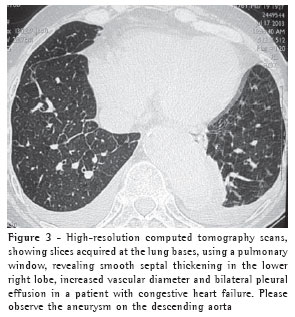

Overall, ground-glass opacities and thickening of the interlobular septa were the most common findings, occurring in 100% of the cases (Figures 1 and 2).

The thickening of the interlobular septa was bilateral in thirteen cases (Figures 1-4) and unilateral in two, also in the patients with fibrosing mediastinitis. In all cases, the thickening was of the smooth type.

Consolidation was detected in only five (33%) of the patients (Figures 2 and 5). All of the patients presented bilateral consolidations, In two cases, the distribution was asymmetric, with a 'bat-wing' aspect, and predominant in the upper right lobe (cases of mitral valve chordae rupture) (Figure 5).

Pleural effusion was the third most common tomographic finding overall and was the most common nonparenchymal finding, being found in 13 patients (87%), predominantly in the bilateral form (n = 11) (Figures 1-3).